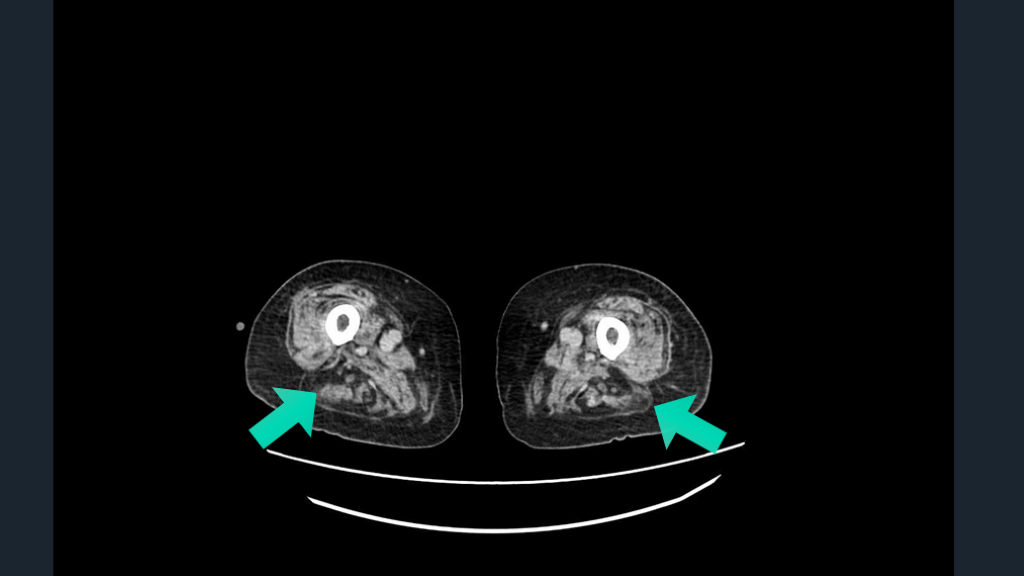

筋障害の評価と筋MRIの重要性

#81.

純粋運動障害を来す筋炎。 筋炎の傍証として、 大腿筋MRIをとってみる。 TIPS

#82.

CASE 比較的突発発症の両下肢麻痺の40歳男性例。 脊髄障害を考慮して脊髄MRI施行するが所見なし。 大腿部痛も訴える。両下肢MMT 2/5。 GBS?脊髄障害?どうする?運動感覚障害とはいい難し。 やや節操ないが、大腿筋MRIを施行し、筋障害を証明した。

#83.

Ann Rheum Dis. 2016;76:681–687. 筋MRI 客観的に筋炎所見があること どの筋に障害があるか? 脂肪変性はあるか? 急性か?慢性か? など、客観的に知ることができる。

#84.

STIR STIR

#85.

客観的な検査に頼る。筋障害を筋MRIでみる。 ERでどこまでやるか?はもちろん議論にはなる。 筋障害は外からみてもわかりにくいこともある。 筋萎縮あるかも???といってもわかりにくい。 筋MRIが教えてくれること:急性筋障害があることの証明。また慢性的な筋障害の証拠(脂肪置換や変性)。 筋力障害が分からないときの筋MRIは一考。 CTでも筋萎縮に注目するのもオススメ。 解説